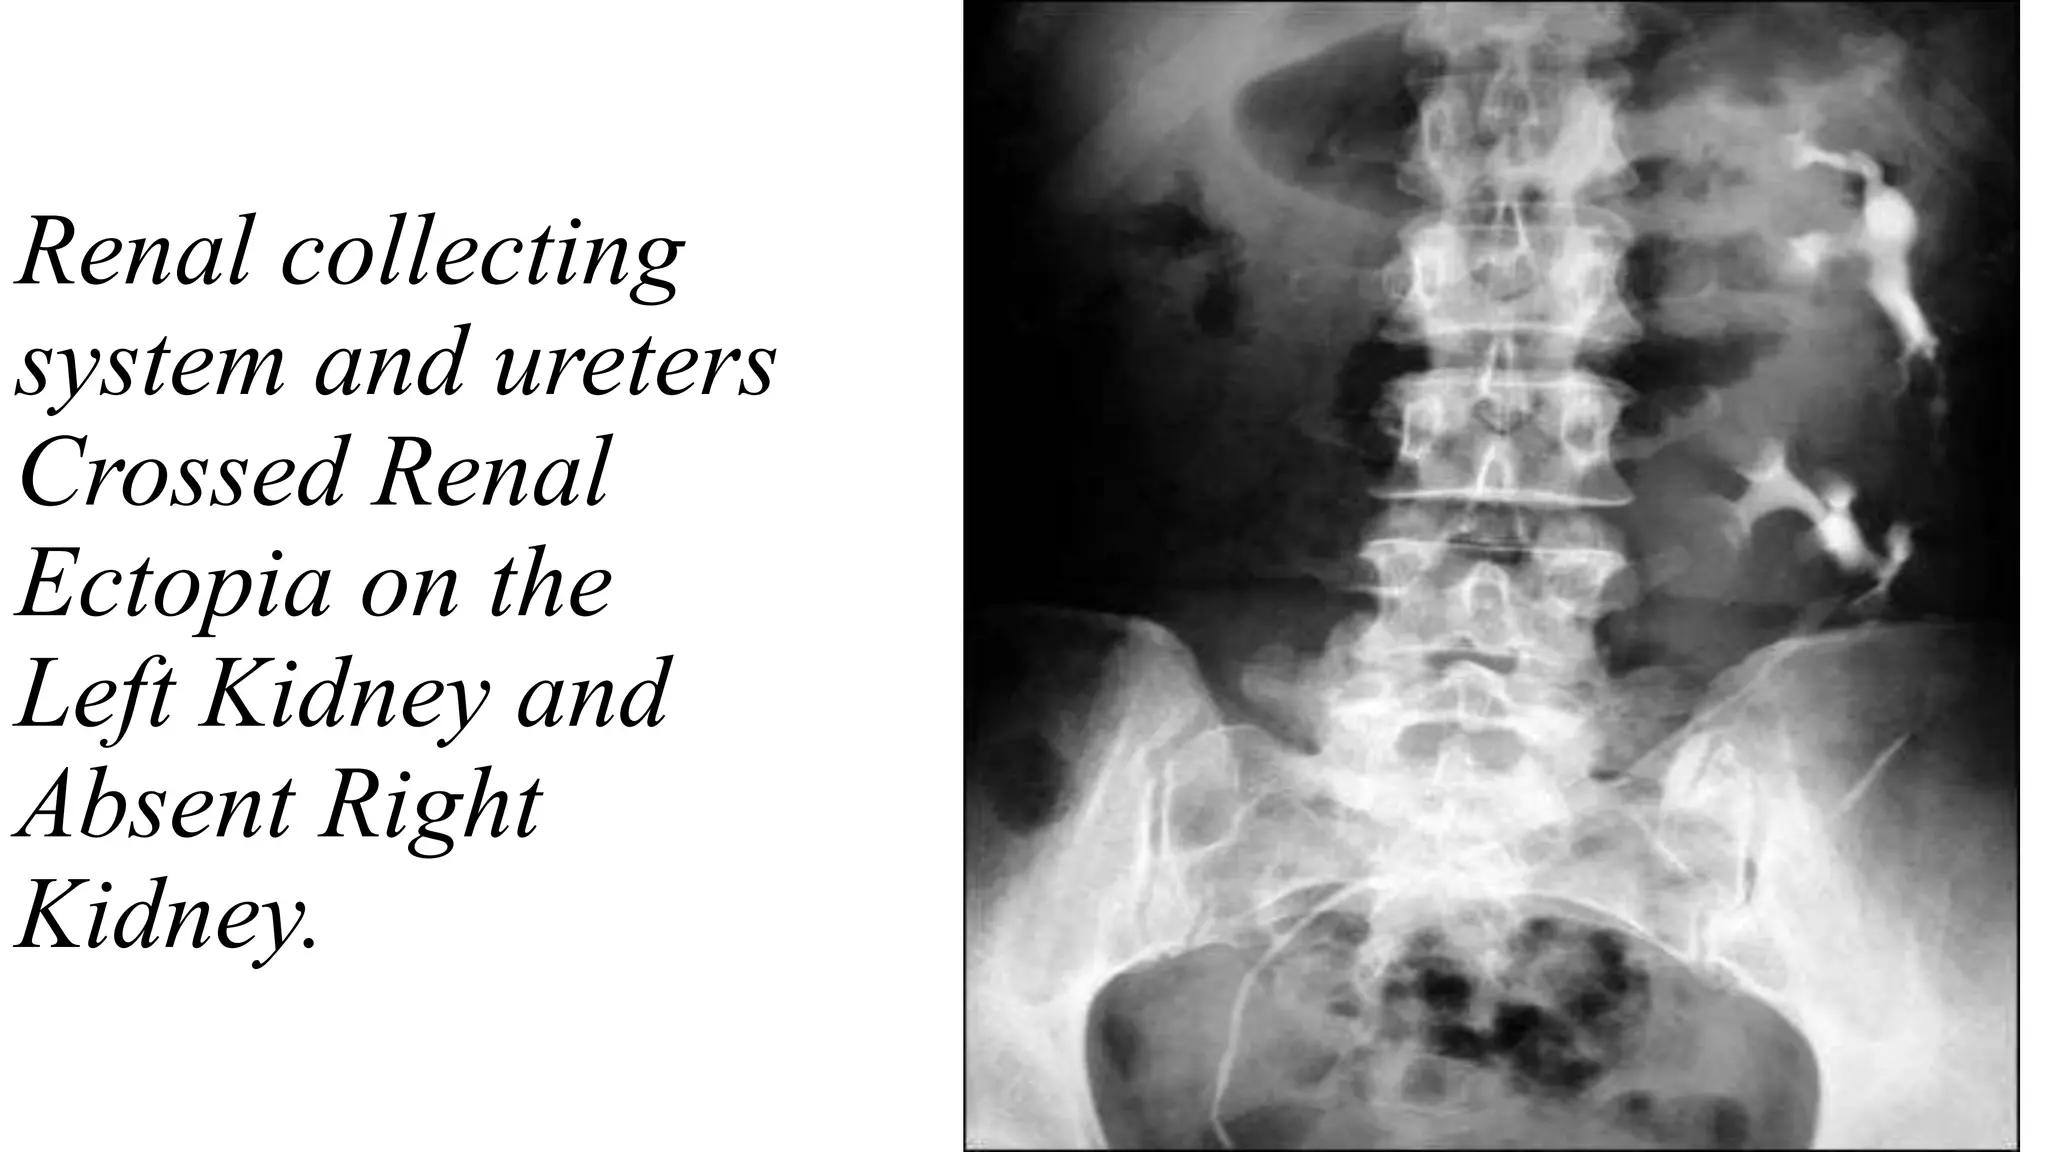

• Dilation of Left

Renal Pelvis and

Calyces Above the

Obstructing

Calculus

Renal collecting

system and ureters

Crossed Renal

Ectopia on the

Left Kidney and

Absent Right

Kidney.

• Dilation ofLeft Renal Pelvis and Calyces Above the Obstructing Calculus

Renal collecting system andureters Crossed Renal Ectopia on the Left Kidney and Absent Right Kidney.